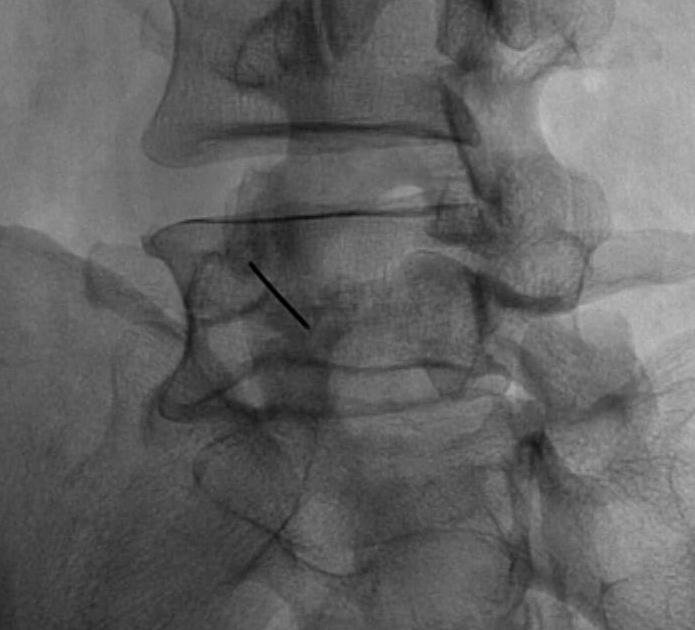

Standing AP and Lateral X-ray

Findings

May miss subtle listhesis on supine XR

- spondylosis

- Meyerding classification

- slip angle

- sacral inclination

Scotty Dog / Oblique Xray

- Ear (superior articular facet) / Nose (TP) / Eye (pedicle)

- Front leg (inferior articular facet) / Body (lamina and body with superimposed SP)

- Tail (superior articular facet of other side) / Back leg (inferior articular facet of other side)

- Neck (Pars and if Collar then has defect)